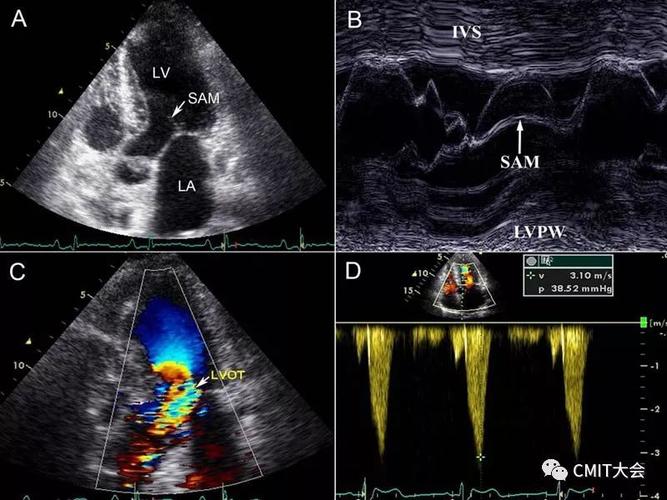

超声可以评估二尖瓣前叶的活动,反应sam征,以了解左室流出道梗阻情况

5,收缩期可见二尖瓣前瓣前向运动,即sam征,部分患者可因此合并二尖瓣

5 平方厘米 室间隔明显增厚者,二尖瓣可出现sam征,心尖区可闻及收缩

二尖瓣sam征示意图

二尖瓣sam征图

sam征超声示意图

sam征超声心动图